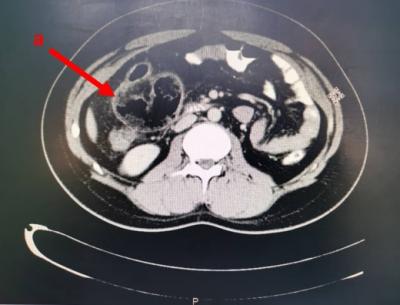

Figure 1: CT abdomen showed dilated loop of terminal ileum at right iliac fossa with fecal intraluminal appearance suggestive of sub-acute bowel obstruction (a) with free air at superior aspect of this loop (b) as well with free fluid seen in right paracolic gutter (c).